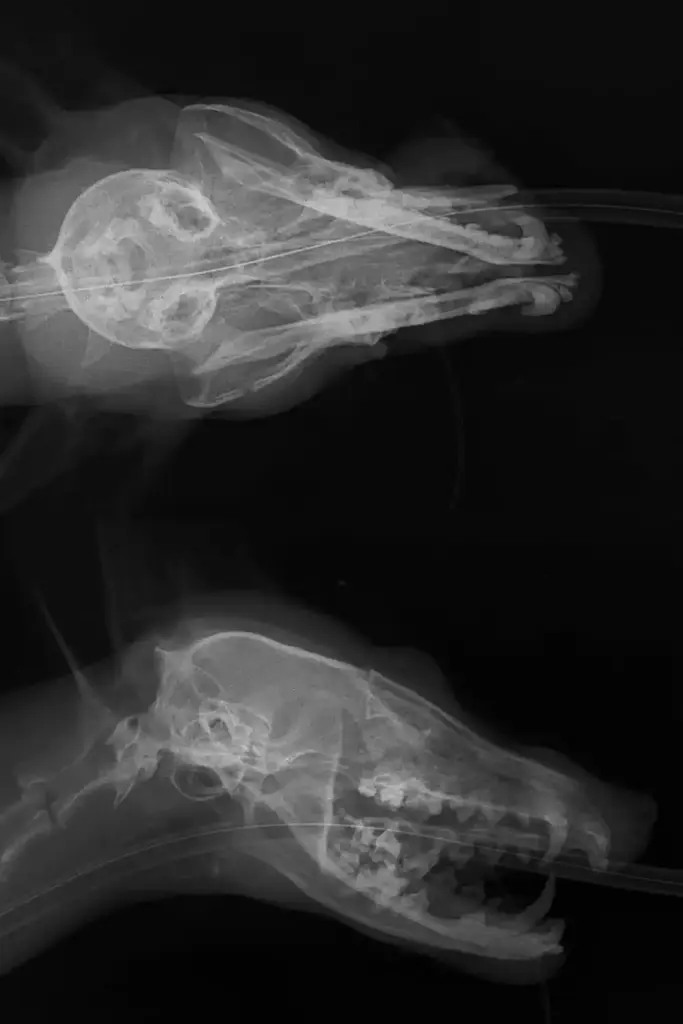

Despite it being gone midnight, Marco (one of our vets) set to work clearing the airways and stabilising her condition before taking an x-ray of her head.

Unfortunately, the result was not good news, with three separate fractures to the jaw and skull. Despite the uphill battle ahead, Marco once again refused to give up on her and we set to work on a plan…